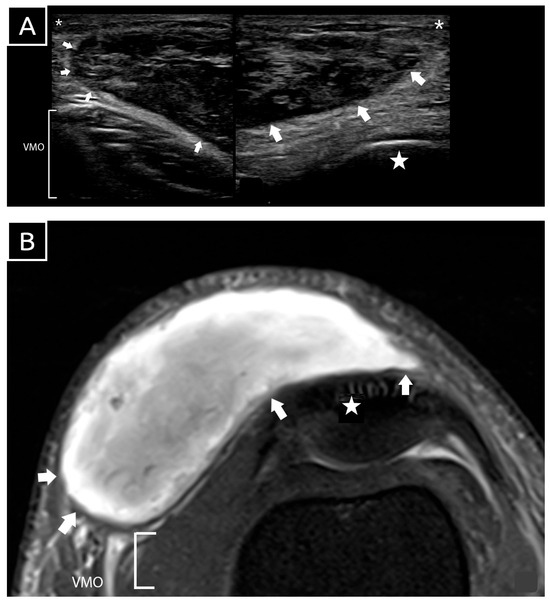

Figure 2. Sonographic image (A) and axial magnetic resonance imaging (MRI) (B) of the patient’s knee after injury. The location, extent, and contents of the MLL (white arrow) were readily visualized on ultrasound. The sonographic image (A) reveals heterogeneous echogenicity suggestive of blood clots, with no fluid component identified within the lesion. Key anatomical landmarks are labeled: VMO (vastus medialis oblique), asterisk (*) denoting the skin and subcutaneous layer, star (★) representing the bony patella, and white arrow outlining the lesion. Image A was obtained via bedside ultrasound using a Philips Lumify with an L12-4 MHz linear probe, operating under factory default settings for frequency, dynamic range, and time gain compensation. The scan demonstrated a large, well-encapsulated hematoma located in the subcutaneous plane, superficial to the bony patella and exerting mass effect on vastus medialis. The lesion measured 13 cm craniocaudally, 10 cm mediolaterally, and had a maximum thickness of 1.33 cm. The internal contents exhibited heterogeneous echogenicity consistent with blood clots, and no fluid component was observed. Power and standard Doppler imaging detected no vascular flow within or around the hematoma, ruling out active bleeding. The vastus medialis appeared normal, with intact echogenic fibers and fascial covering, showing no signs of injury. The clinical and imaging findings were consistent with a diagnosis of an MLL of the knee. The patient remained hemodynamically stable during hospitalization, with normal laboratory values, including hemoglobin, platelet count, and clotting profiles. An ultrasound-guided aspiration was performed under aseptic conditions using a wide-bore (19 G) needle to target multiple areas of the lesion. No fluid was aspirated, as the lesion comprised primarily blood clots. The patient was managed conservatively with wound dressing, compressive bandaging, ice therapy, non-steroidal anti-inflammatory drugs, and a hinged knee brace locked at 0 degrees to protect soft tissues and minimize shear stress on the hematoma. The patient was allowed full weight-bearing walking exercises while wearing the brace, but excessive walking was restricted. Outpatient follow-up included daily dressing changes and renewal of the compressive bandage to maintain effective compression. MLLs are commonly associated with high-energy trauma and frequently occur alongside fractures of the proximal femur, pelvis, and acetabulum. These traumatic events can lead to the separation of the skin and subcutaneous tissues from the underlying fascia, resulting in the formation of these lesions. Letournel and Judet [1] emphasize the incidence of MLLs in acetabular fractures, indicating that approximately 8.3% of patients with acetabular fractures also experience these lesions. This highlights the importance of recognizing MLLs in the context of severe orthopedic trauma. A systematic review by Shen et al. [2] found that males are roughly twice as likely to experience these lesions compared to females, reflecting the higher incidence of polytrauma among men. However, MLLs are often undiagnosed or diagnosed late, suggesting that their true prevalence may be significantly underestimated.